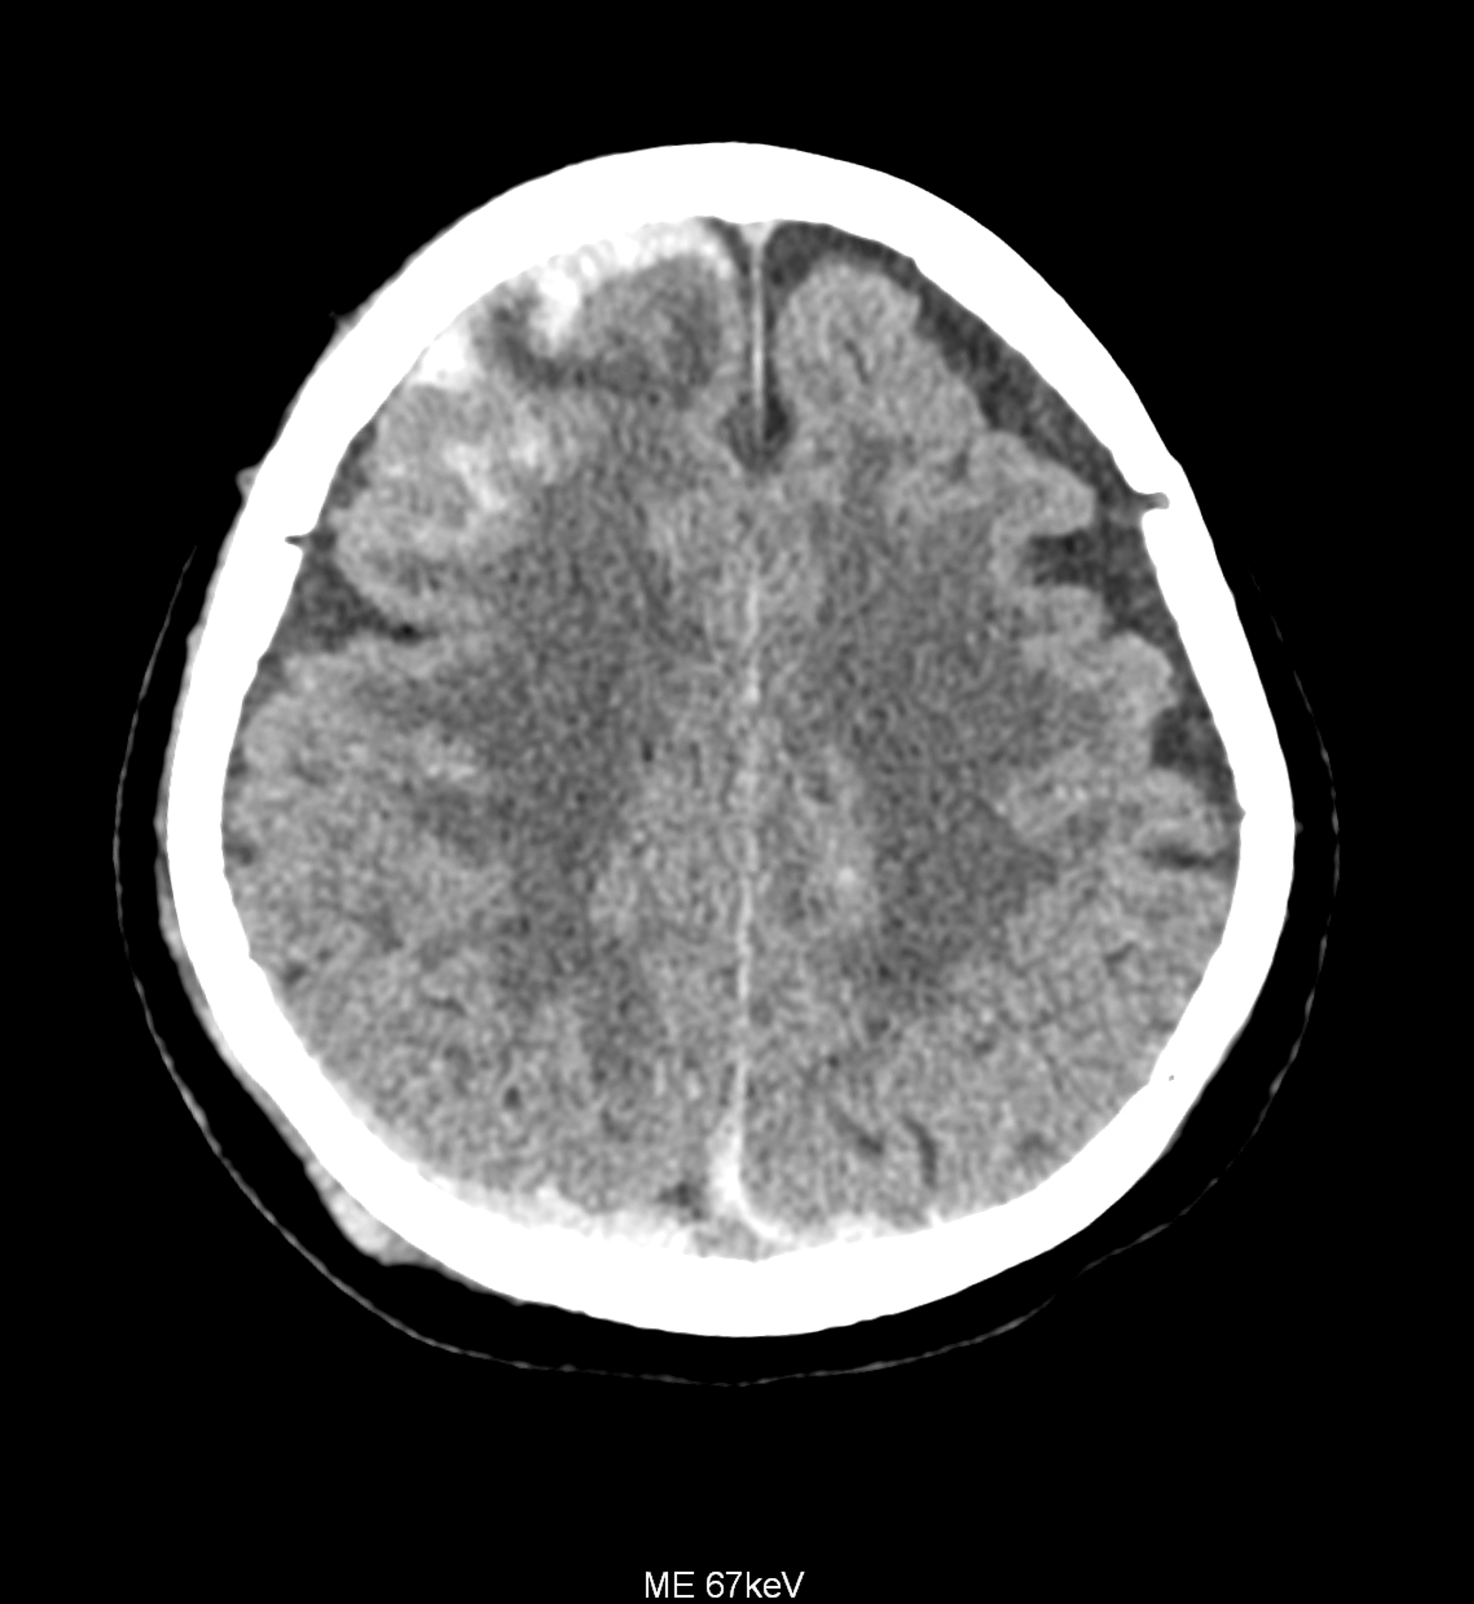

Bleeding is characterized by different absorption characteristics than healthy brain tissue (both gray and white matter) and cerebrospinal fluid. Due to the higher proportion of proteins with amino acids with disulfide bonds, the signal intensity increases at higher energies, making it possible to use monoenergetic imaging at energies above 140 keV, and/or virtual non-contrast. The hemorrhage then becomes more hyperdense, while the rest of the brain tissue acquires a uniform low signal. In addition to bleeding, areas of extracellular fluid of vasogenic origin are also imaged, i.e., in areas around contusion-type brain tissue injuries.

An example of the use of spectral imaging in complex brain injury, where contusions, diffuse axonal injury, subarachnoid hemorrhage, subdural hemorrhage, and blood in the ventricular system are present.

comparison of the images with the energies of monoenergetic reconstructions 40 keV, 67 keV (standard conventional reconstruction), 190 keV and virtual non contrast (VNC)